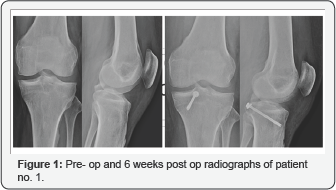

The mean follow-up period was 8(range, 4-12) months. All patients achieved union at mean 12(range, 10-14) weeks. VAS scores reduced from mean 6(range, 5-7) to mean 1(range, 0-2) at 6 weeks postoperatively. None of the patients required regular analgesia in the post operative period beyond the first week. The range of movement (ROM) improved from mean 96.60 to 113.30. Full extension was achieved in all patients while 1 patient had restriction of terminal flexion at 3 months post operatively. All which improved to no laxity in 3 cases and grade I laxity in 1 4 patients had grade III posterior drawer test pre-operatively case. There were no wound complications (Figure 1‐3).

Lysholm scores preoperatively ranged from 69 to 79 (mean 74.5). This improved to a mean postoperative Lysholm score of 91(range 88‐94). All the patients were back to their pre‐injury level of activities after 6 months of surgery except one patient who is still to complete her 6 month follow-up Table 1.